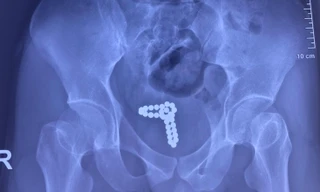

TPO - Đang thử 'cảm giác lạ' thì chuỗi bi kim loại tuột vào niệu đạo khiến nam thanh niên phải nhập viện cấp cứu trong tình trạng tiểu xuất huyết. Các bác sĩ đã phải mổ bàng quang, lấy dị vật ra ngoài.